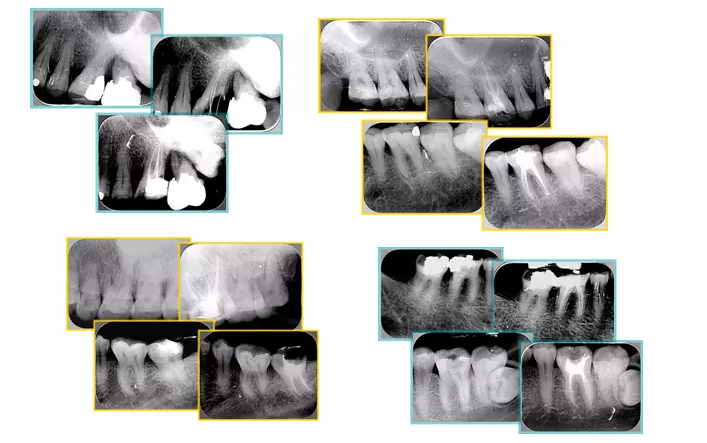

共有 4 張 X 線片,分別是術(shù)前、診斷絲 、主牙膠尖確認(rèn)、術(shù)后。

( 1 )術(shù)前:術(shù)前 X 線片用來了解牙齒的大概情況。術(shù)前預(yù)期為多根牙時 X 線片應(yīng)偏頭拍攝。

( 2 )診斷絲:根據(jù)術(shù)前 X 線片進(jìn)行開髓、根管的初步預(yù)備后,需要插入診斷絲,用來指示工作器械位置。常用 10 號或 15 號擴(kuò)大器作為診斷絲插入牙髓腔。

( 3 )主牙膠尖確認(rèn):通過術(shù)前預(yù)期和診斷絲診斷,明確工作長度、牙根走向,進(jìn)行根管預(yù)備。之后應(yīng)進(jìn)行主牙膠尖(中銼)確認(rèn),已明確根管是否適合充填。

( 4 )術(shù)后:觀察治療效果。